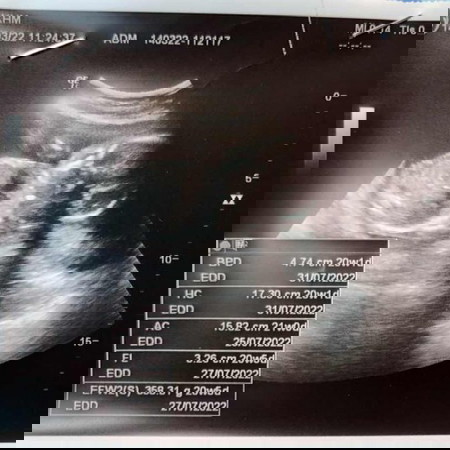

แม่งงมากเลยนับกับหมอที่ฝากท้องตอนนี้จะได้15w3d แต่พอซาวด์วันนี้ 20w1d เฉยเลยค่า ช่วยดูหน่อยจ้า

น้องตัวใหญ่กว่าอายุครรภ์จริง ผลซาวด์เลยออกมาเป็น20wค่ะ ปกติคุณหมอจะยึดจากผลซาวด์ครั้งแรกหรือวันที่ประจำเดือนหมดครั้งสุดท้ายเป็นหลักค่ะแม่

ยึดที่หมอคำนวนครั้งแรกค่ะ ในใบซาวอายุครรภ์จะตามขนาดตัวน้อง บางทีน้องตัวใหญ่กว่าอายุครรภ์